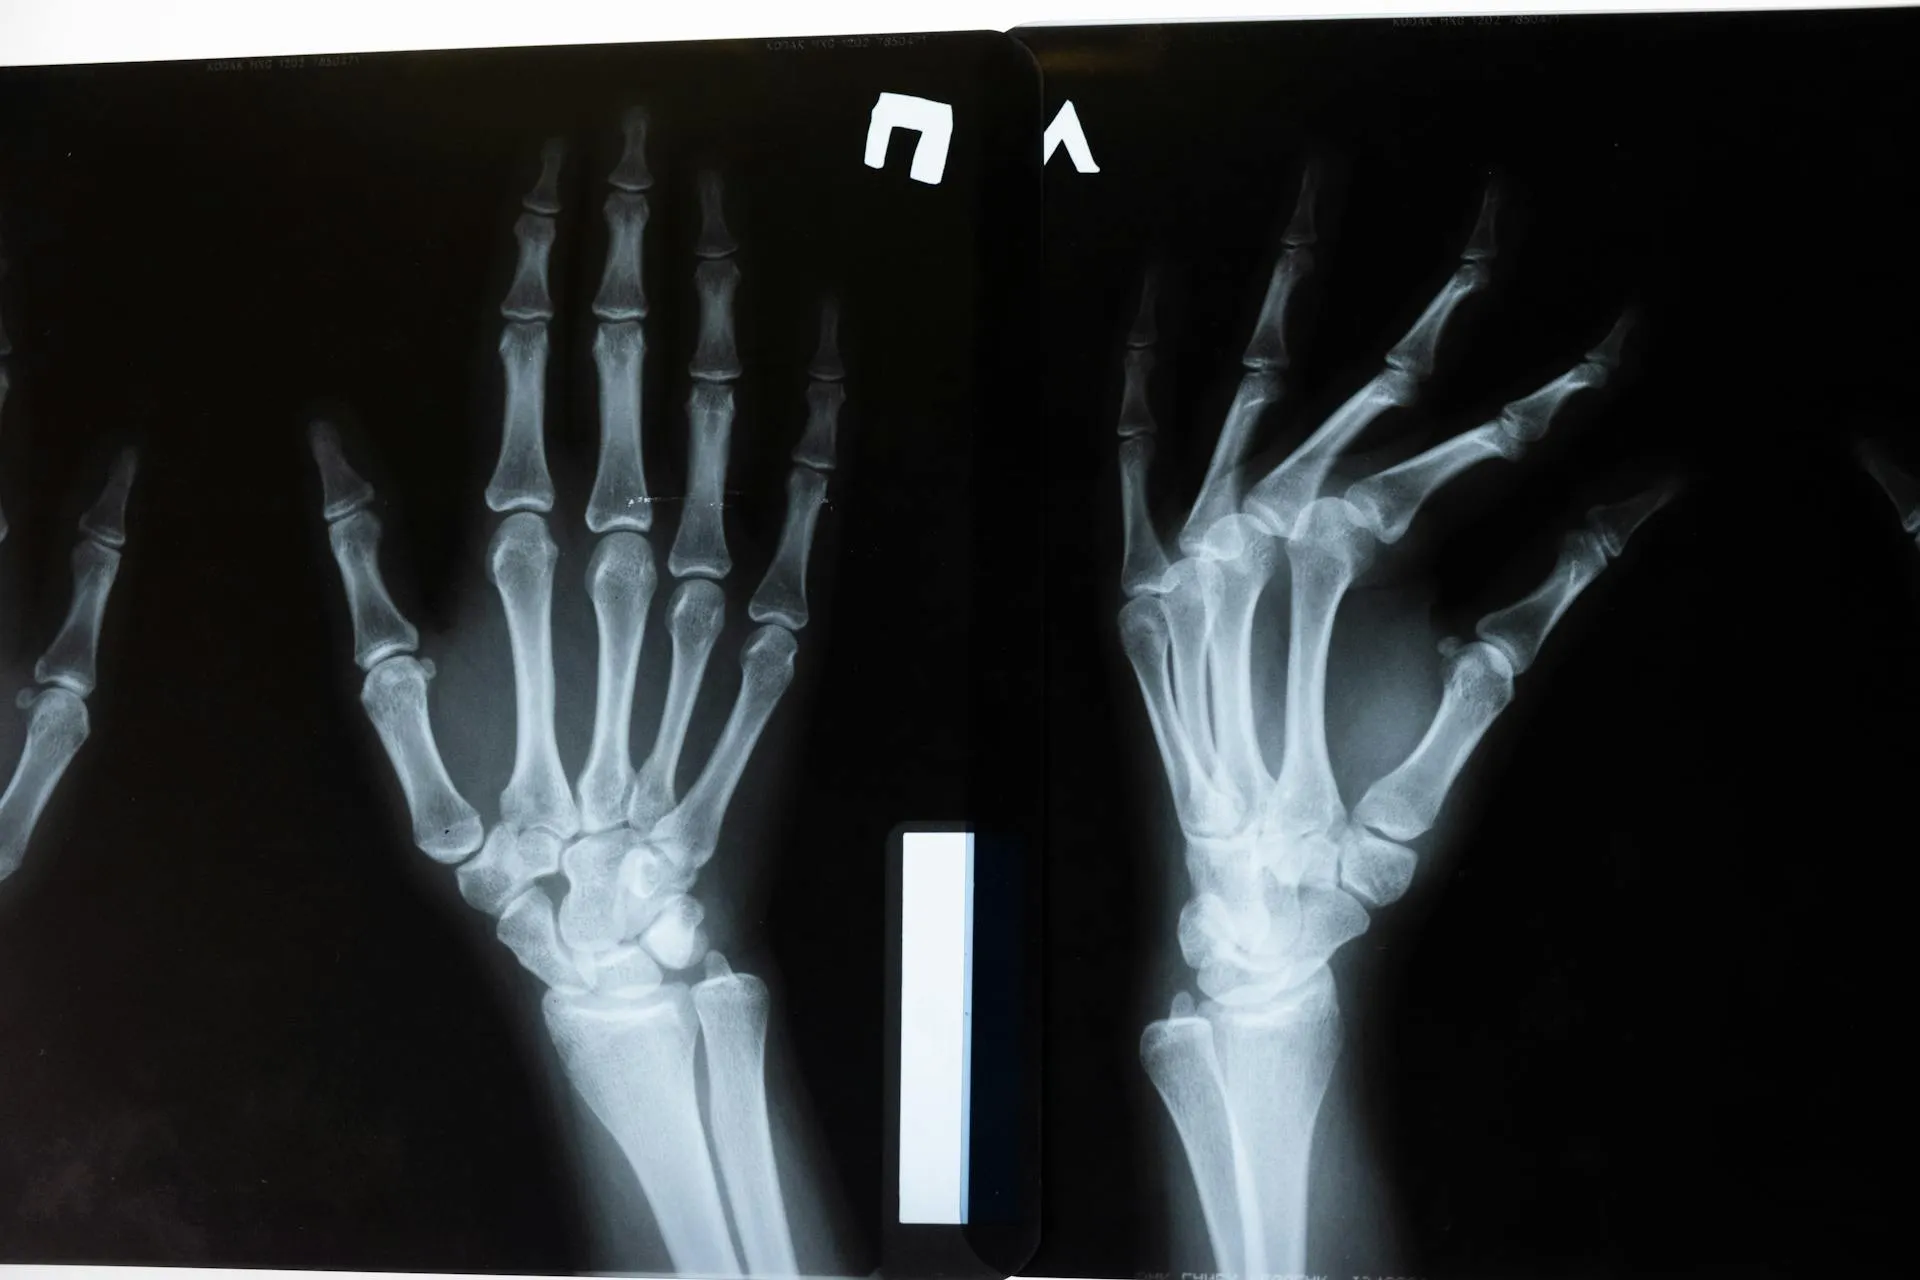

W uproszczeniu RTG działa na zasadzie przenikania promieniowania rentgenowskiego przez ciało. Każda tkanka pochłania je w innym stopniu. Kości, ze względu na swoją gęstość, zatrzymują więcej promieni, dlatego na zdjęciu są jasne. Narządy wewnętrzne i miękkie tkanki: ciemniejsze. Na podstawie uzyskanego obrazu lekarz może ocenić stan struktur wewnętrznych i postawić wstępną diagnozę. Badanie jest krótkie, bezbolesne i nieinwazyjne. Wykonywane najczęściej przy podejrzeniu złamań, zwyrodnień, chorób układu oddechowego, schorzeń kręgosłupa czy problemów z przewodem pokarmowym.

W zależności od rodzaju badania, możemy zostać poproszeni o zdjęcie ubrania z określonej części ciała i założenie jednorazowego fartucha. Niektóre badania wykonuje się na leżąco, inne w pozycji stojącej lub siedzącej. Technik ustawia nas precyzyjnie względem aparatu. Tu kilka centymetrów ma znaczenie. Czasem trzeba wstrzymać oddech, czasem obrócić głowę. A potem… klik. Dosłownie kilka sekund i wszystko gotowe. W niektórych przypadkach wykonuje się kilka ujęć z różnych perspektyw np. w przypadku złamań czy kontroli ortopedycznych.